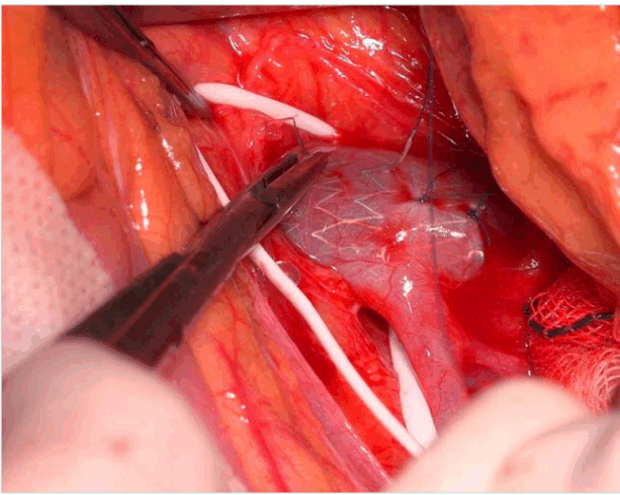

Renocaval bypass: A considerable number of patients undergo restenosis and occlusion of the transposed vein and require reintervention. The renocaval bypass technique employs the great saphenous vein to construct a bypass and does not require transposition of the LRV. The saphenous vein is anastomosed proximally to the IVC, below the LRV, and distally to the LRV. Both anastomoses are performed with partial clamping so that they have little effect on venous hemodynamics. The advantages of this operation are the short period of renal ischemia and few anastomoses and no need to ligate the lumbar veins, the gonadal vein, or the LRV if they are not refluxing, since they do not affect the anastomoses. However, owing to the risk of shortening, restenosis, or collapsing of the saphenous vein graft because of the aorta, the renocaval bypass with prosthetic graft is the preferred technique in adult patients with significant collaterals and unfavorable anatomy. For this purpose, ringed reinforced polytetrafluoroethylene (PTFE) grafts are used to connect the LRV to the IVC with a C-Shape (Figure 3). Deser et al report successful use of a PTFE prosthetic graft for renocaval bypass in a patient with posterior NCS.36 Furthermore, Morata renal failure, or varicocele. Common procedures include renal vein transposition, gonadal vein transposition, renocaval bypass, venous bypass, renal autotransplantation, and endovascular stenting.34 et al reported over 40 procedures and more than 6 years of follow-up with PTFE graft renocaval bypass.29 Severe thrombotic or stenotic complications occurred in only 11% of these patients. They also highlighted that it is essential to cover the bypass graft with an omental flap (epipoplasty) to prevent duodenal fistula risk. The advantages of this operation are the short period of renal ischemia and few anastomoses, with high rates of symptomatic resolution, especially for complaints of hematuria and flank pain, and it is considered the gold standard treatment for NCS.29,34,35

Figure 3. Renocaval bypass using ringed reinforced prosthetic polytetrafluoroethylene (PTFE) graft with transperitoneal approach.